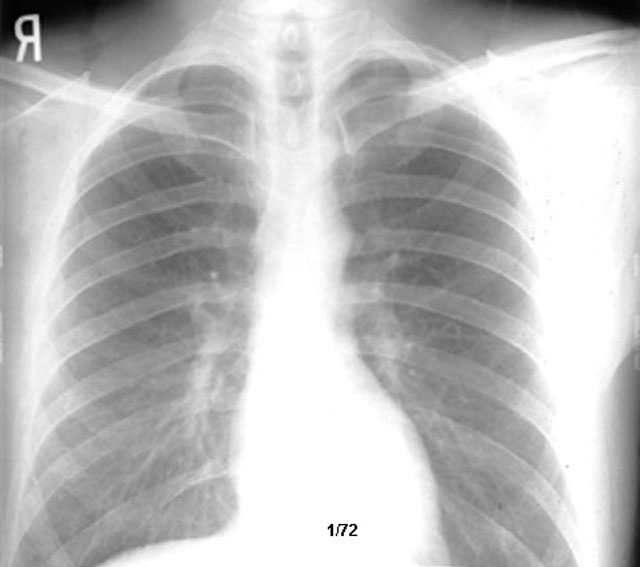

Eosinophilic Granuloma

• Interstitial markings

• Reticulonodular

• Slight reduction in lung volume compared to old film (count the ribs to diaphragm)

• Full hilum and prominent azygous node

Review old x-ray below.